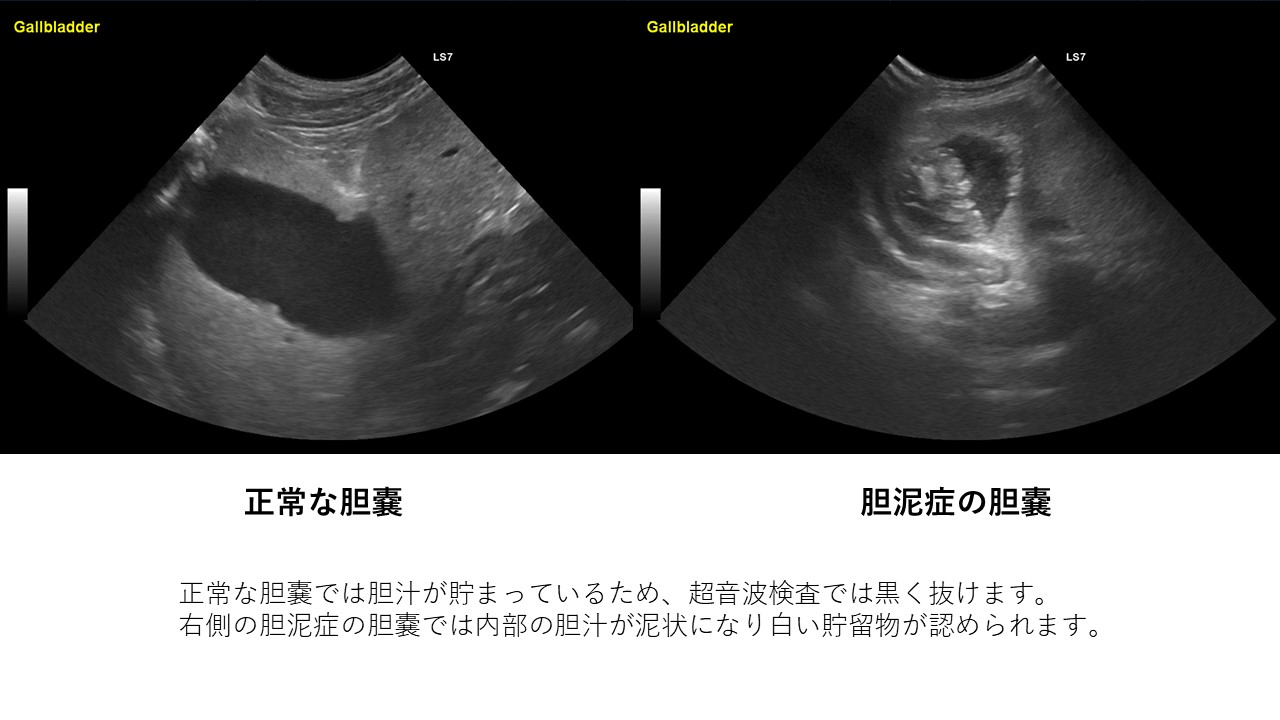

胆泥症は無症状で経過することが多いため、定期的な健康診断で早期発見を心がけましょう。 また、胆嚢炎や内分泌疾患( 甲状腺機能低下症 や 副腎皮質機能亢進症 )などのような、

胆泥症・胆石症について 胆嚢は、胆汁を産生し貯留する器官です。 胆汁には、脂肪を分解し水に溶けやすい状態に(乳化)する役割を持っています。 胆嚢に貯えられた胆汁は、元々サラサラの水胆泥を生じさせた原因や疑われる原因があれば、それを取り除きます。 そのために、 犬の胆泥症 <前編> で説明した原因追及のための検査結果が重要になります。 肝臓の異常が認められるので